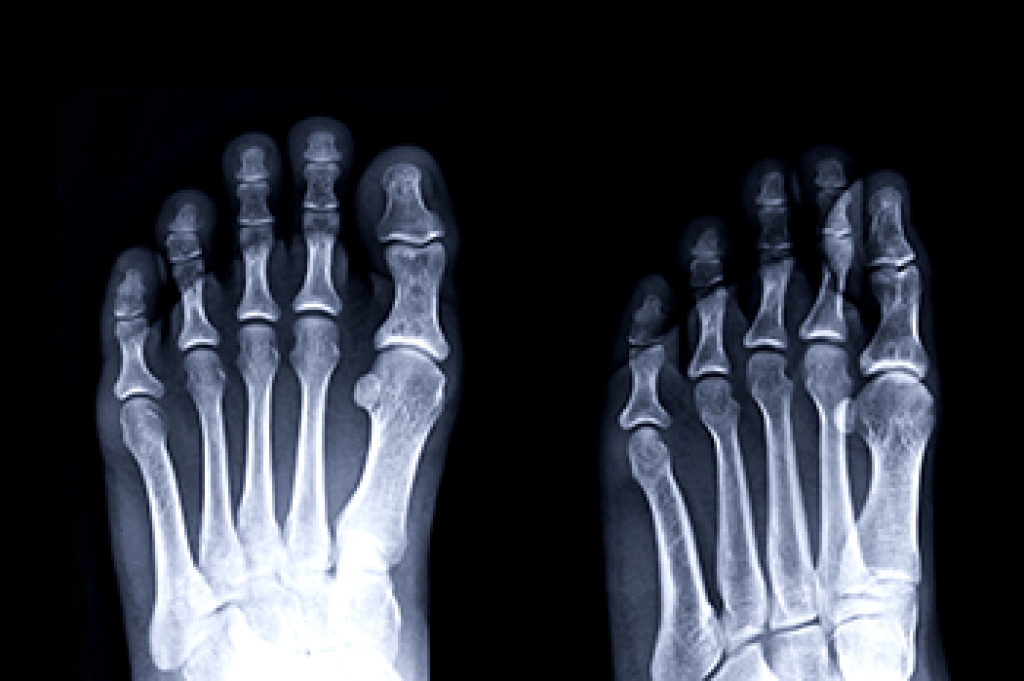

Metatarsal fractures refer to breaks or cracks in one or more of the five long bones in the foot that connect the ankle to the toes. These fractures often result from direct trauma, overuse, or severe twisting of the foot. Symptoms include pain, swelling, bruising, and difficulty bearing weight. Proper treatment is vital for healing, as improper or delayed treatment can lead to serious consequences. Without appropriate care, metatarsal fractures can result in chronic pain, improper bone healing, and long-term mobility issues. Misaligned bones can cause persistent discomfort and increase the risk of arthritis in the affected joints. Therefore, it is essential to seek prompt attention from a podiatrist, follow prescribed treatment plans, and allow adequate time for healing to prevent complications and ensure a full recovery. If you have believe you have fractured a metatarsal, it is strongly suggested that you visit a podiatrist for a diagnosis and treatment.

A broken foot is caused by one of the bones in the foot typically breaking when bended, crushed, or stretched beyond its natural capabilities. Usually the location of the fracture indicates how the break occurred, whether it was through an object, fall, or any other type of injury.

Those that suspect they have a broken foot shoot seek urgent medical attention where a medical professional could diagnose the severity.

Treatment for broken bones varies depending on the cause, severity and location. Some will require the use of splints, casts or crutches while others could even involve surgery to repair the broken bones. Personal care includes the use of ice and keeping the foot stabilized and elevated.